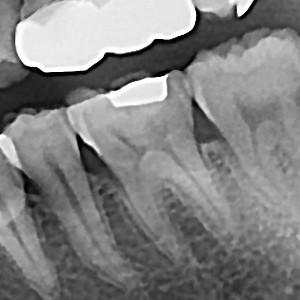

충치치료&신경치료 하루에 끝나는 신경치료

60bab75a1a70db4a6fd0ef2b4df1f9ae_1767345003_5941.jpg